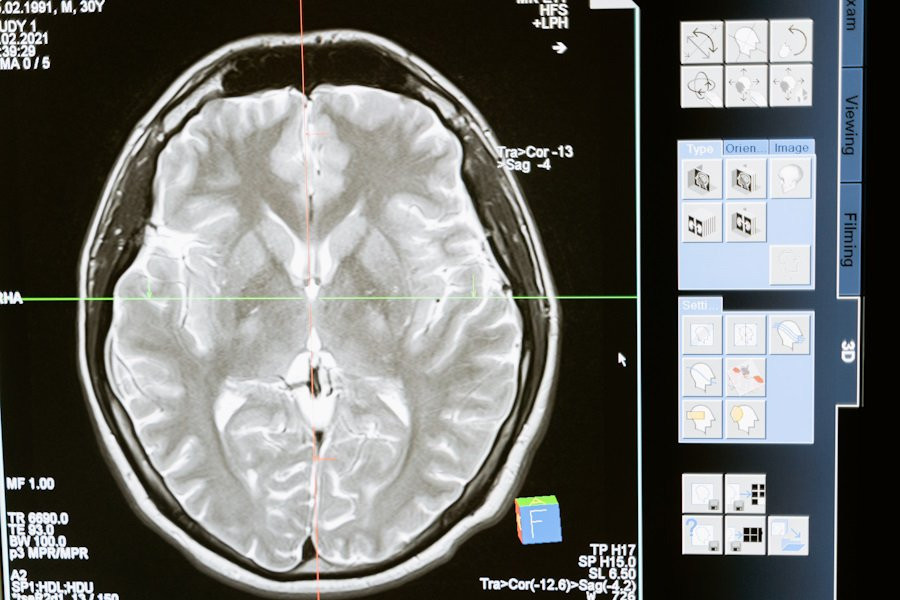

Фото из открытых источников

Исследователи из Institute for Basic Science (IBS) (Республика Корея) провели успешные испытания новой методики Magnetogenetic Interface for NeuroDynamics (Nano-MIND), которая позволяет воздействовать на мозг человека без использования имплантатов. Эта технология объединяет магнитные поля и намагниченные наночастицы, что открывает новые возможности для нейромодуляции, сообщает портал Nature.

На сегодняшний день наиболее распространенными методами управления нейронной активностью являются оптогенетика и глубокая стимуляция мозга. Оптогенетика использует свет для активации клеток мозга, а глубокая стимуляция мозга применяется, например, для лечения болезни Альцгеймера. Однако оба метода требуют использования имплантатов.

Технологии нейромодуляции играют ключевую роль в исследовании связей и функций мозга. Магнитная нейромодуляция предлагает беспроводную и удаленную глубокую стимуляцию мозга, что делает её уникальной по сравнению с оптогенетикой и проводными электродами. Ранее использование магнитных подходов было ограничено из-за недостаточного понимания их работы и плохо спроектированных систем.

Методика Nano-MIND использует намагниченные наночастицы и технологию Cre-loxP для избирательной активации генетически закодированных ионных каналов Piezo1 в целевых популяциях нейронов. Это позволяет точно контролировать активность нейронов глубокого мозга как in vitro, так и in vivo.